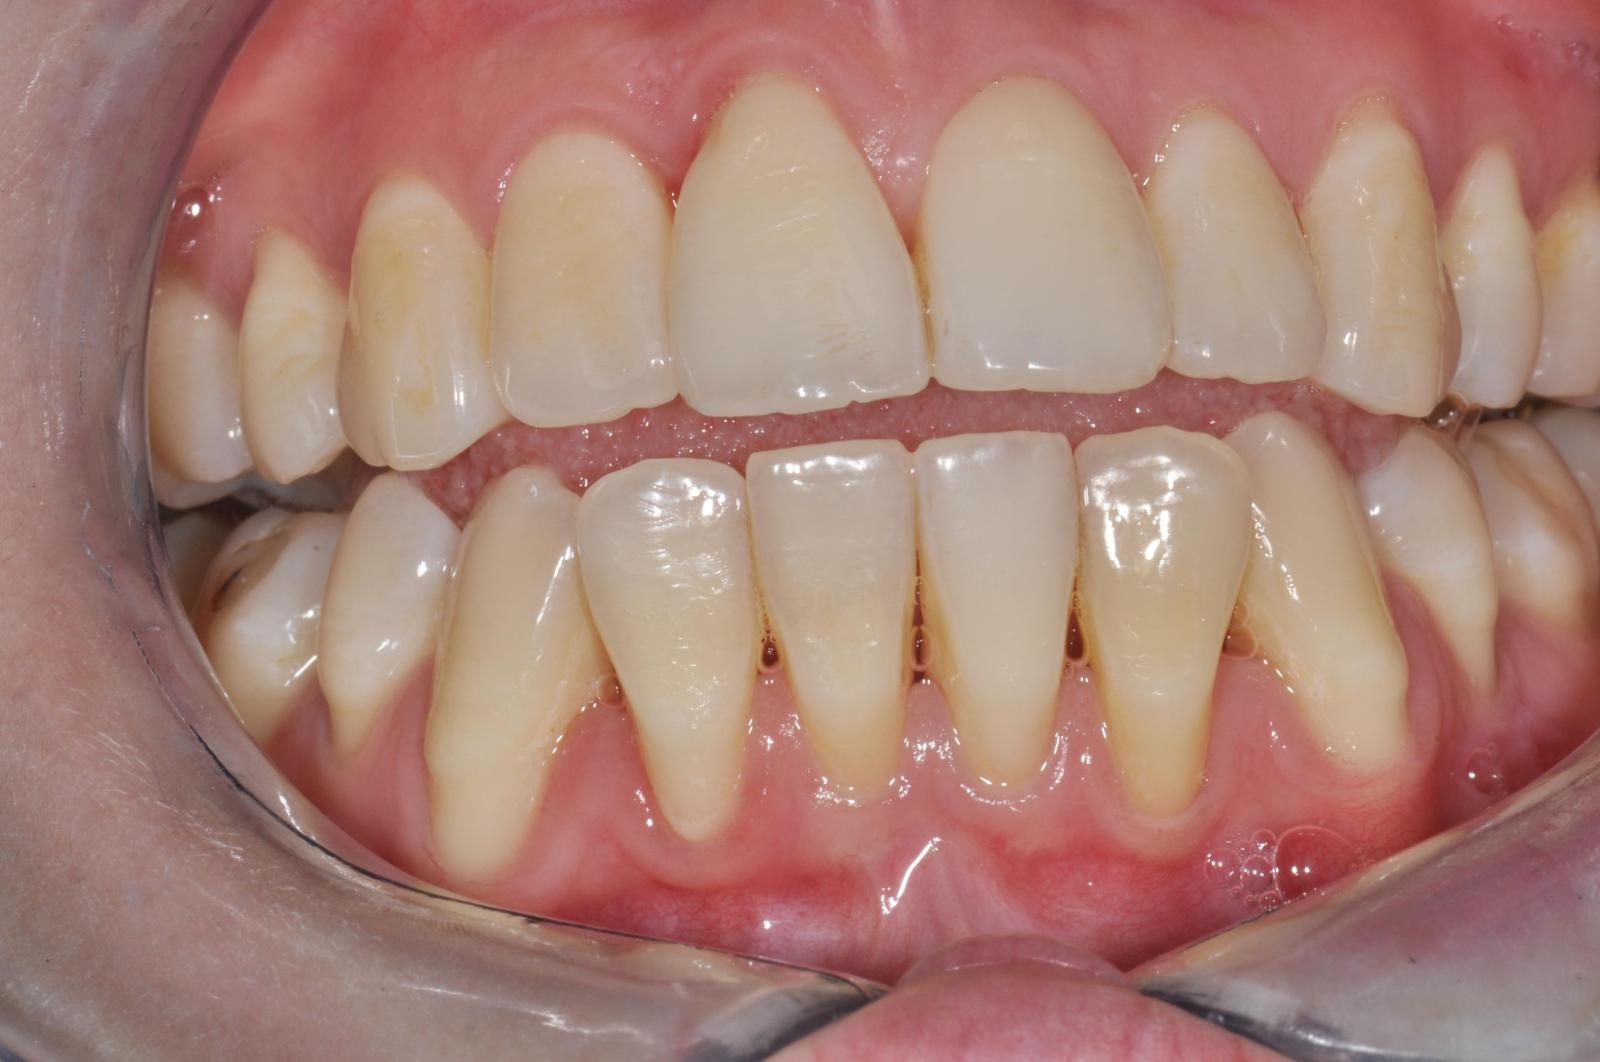

Le sourire gingival est appelé Gummy Smile. Il s’agit d’une situation lors de laquelle la gencive descend trop bas sur les couronnes des dents, soit les parties qui sont normalement visibles lorsqu’on sourit.

Cela se traduit par des gencives proéminentes et des dents qui semblent plus courtes. Bien entendu, cela nuit à l’apparence du sourire.